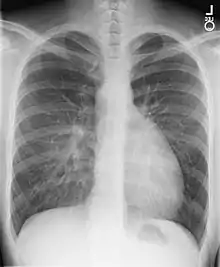

Transposición de los grandes vasos

Los signos y síntomas de una transposición de grandes vasos aparecen inmediatamente después de cortar el cordón umbilical del recién nacido y dependen del tipo y del tamaño del defecto. El signo clásico es la cianosis (el color azul de la piel) asociada con dificultad respiratoria. Por lo general se detecta un soplo cardíaco que manifiesta un posible defecto congénito.